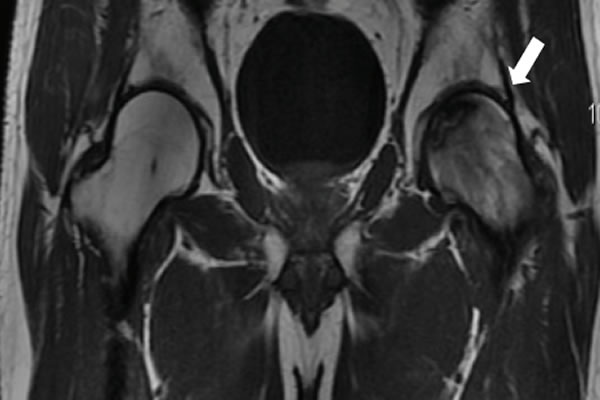

Enfermedades Óseas Osteopenia - Osteoporosis Enfermedades Óseas Calcio y Vitamina D Enfermedades Óseas Fracturas por Fragilidad Enfermedades Óseas Enfermedad de Paget Enfermedades Óseas Osteomalacia Raquitismo Enfermedades Óseas SME Doloroso Reg Complejo Enfermedades Óseas Necrosis ósea avascular Enfermedades Óseas Enfermedades Óseas poco Frecuentes Enfermedades Óseas Displasia Fibrosa Enfermedades Óseas Otras Enfermedades Óseas